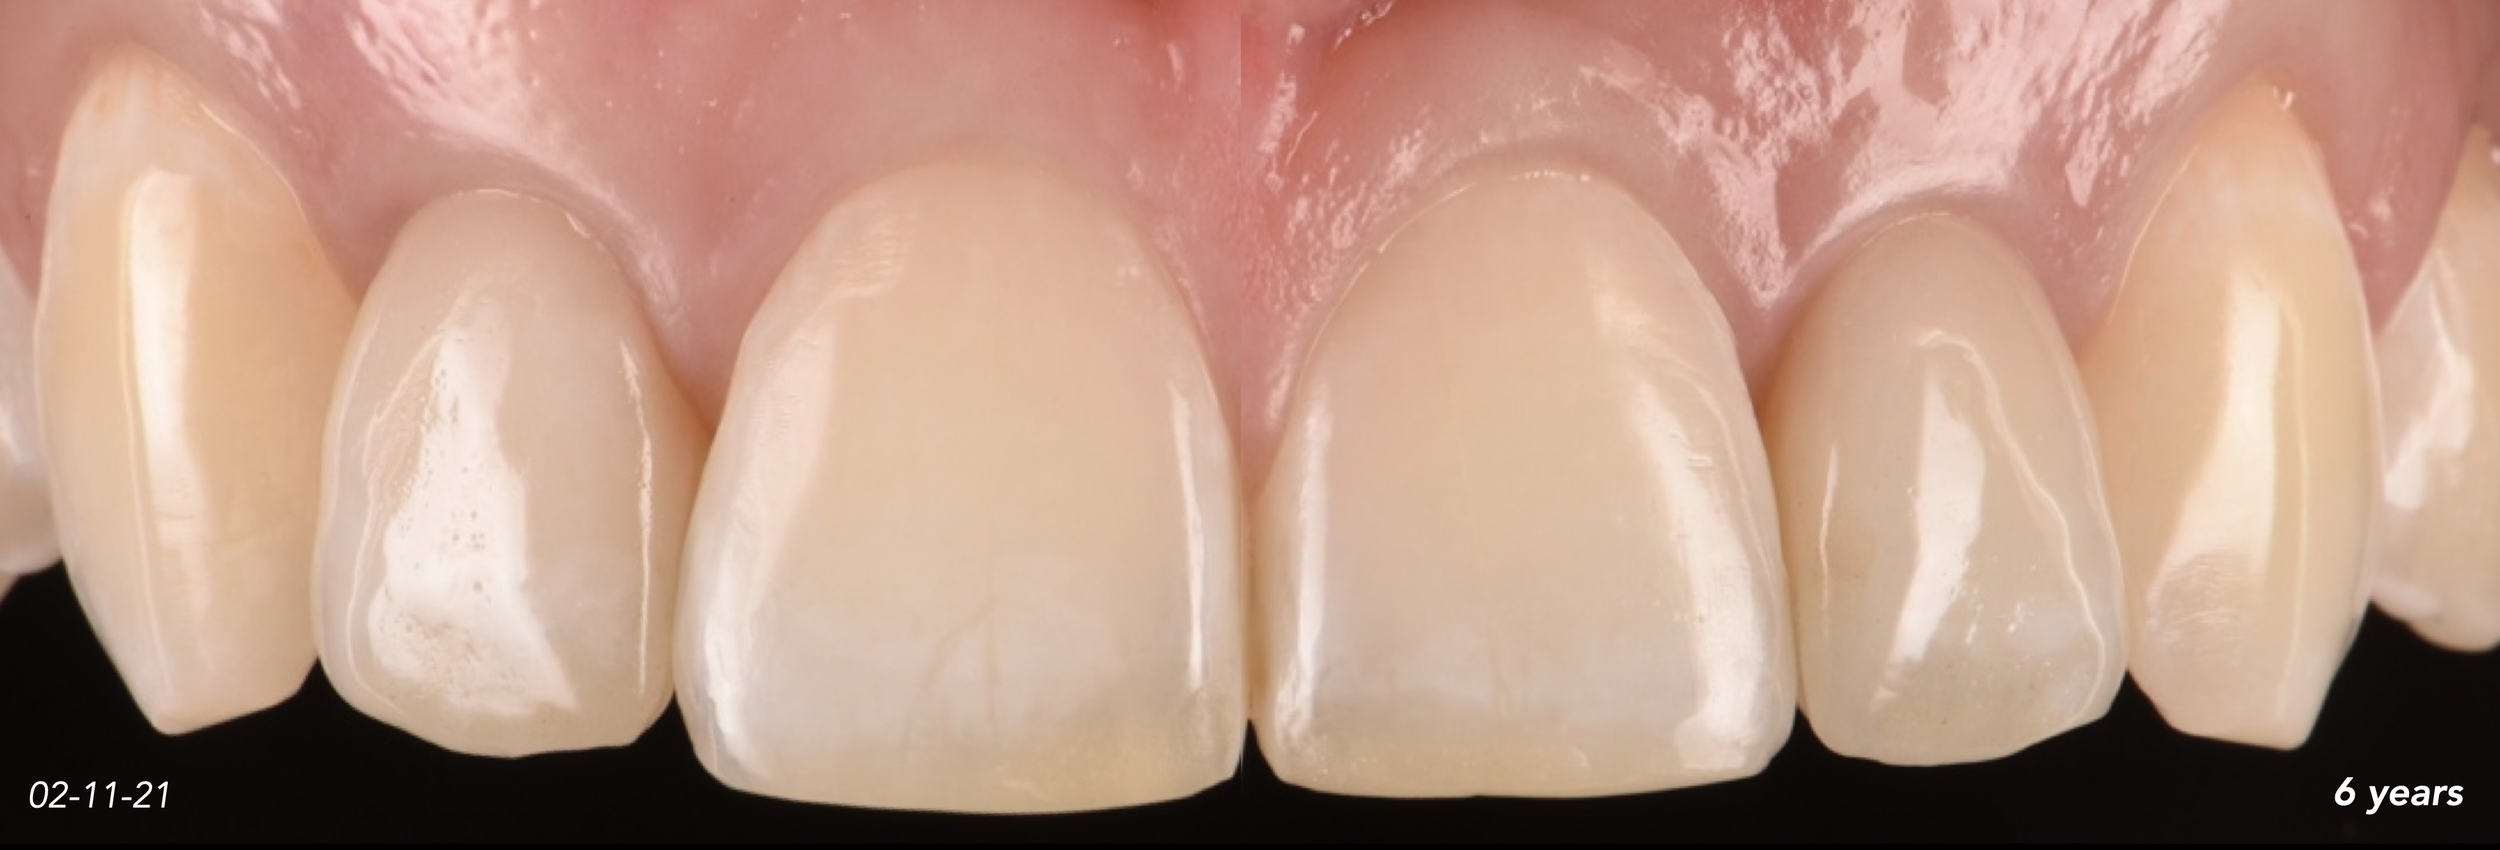

CASE 2. CONGENITALLY MISSING LATERAL INCISORS